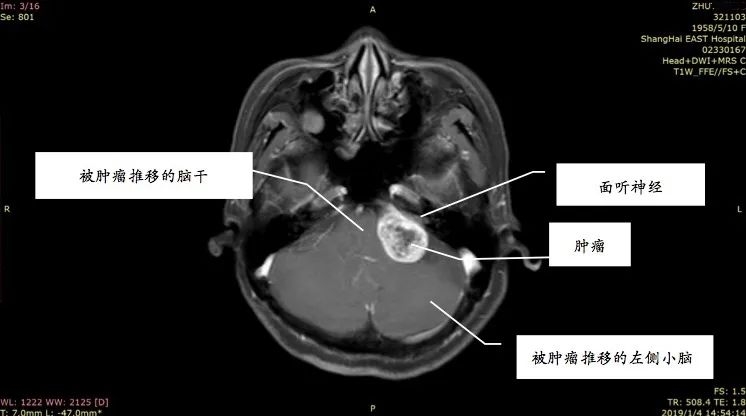

姚先生打电话时总听不清对方讲话,右边耳朵像有蜜蜂在飞,发出嗡嗡的声音。起初并没太在意,以为是工作繁忙劳累或情绪紧张,休息一会儿也就好了。前段时间他感觉耳鸣越来越厉害,并且还出现听力下降、失眠等症状,到医院做了头部的核磁共振增强扫描,发现他患上了听神经瘤。

听神经瘤是指起源于听神经鞘的肿瘤,为良性肿瘤,确切的称谓应是听神经鞘瘤,是常见颅内肿瘤之一。事实上,三分之二以上的人都出现过耳鸣的现象。那么,普通的耳鸣、脑中风的耳鸣与听神经瘤的耳鸣又有何区别呢?

听神经瘤引发的耳鸣

主要是单侧耳鸣,且音调较高,类似蝉鸣声、蟋蟀声,或者金属磨擦声。随着肿瘤越来越大,就可能压迫到周围神经,还也可能出现面部麻木、面肌痉挛、感觉异常、头晕,甚至走路不稳、瘫痪等类似脑中风的症状,且各项症状持续加重没有缓解。

据统计,临床上57%的听神经瘤患者会出现耳鸣等症状,其中26%的患者表现为突发性耳聋。随着肿瘤的生长,患者可能出现听力下降,甚至完全消失。但也不用太恐慌,听神经瘤只要及时接受科学治疗,并不会对患者造成严重危害。只要能够及时手术,切除肿瘤,患者多数可以获得较好的预后,并且听力有可能恢复。